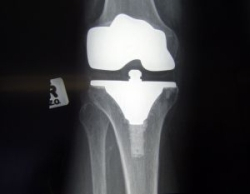

Pri neúspechu farmakologickej a nefarmakologickej liečby a ťažkých formách osteoartrózy sa uplatňujú chirurgické výkony. Indikáciou operačného výkonu sú trvalé silné bolesti a výrazné obmedzenie funkcie postihnutého kĺbu.